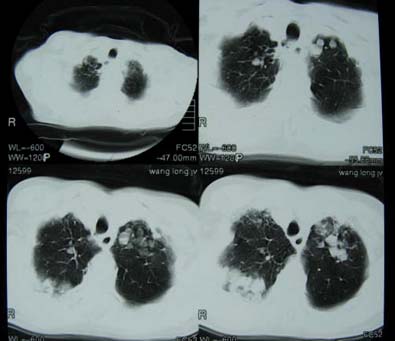

肝癌、肺转移。

肝癌、肺转移 支持

考虑为wg肉牙肿

肺转移瘤,肺泡细胞癌,播散性肺结核都有可能的.说不好还是金葡菌感染呢